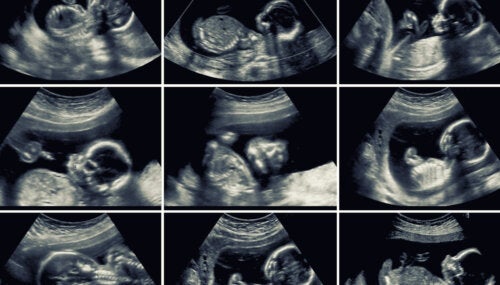

Du skal være mor, så glad, fuld af håb og samtidig også fuld af spørgsmål. Træk vejret dybt og mist ikke dit smil, for her på Børnenes verden vil vi hjælpe dig med at finde på en plan. Du vil have al den information, du skal bruge de næste 9 måneder: lægeundersøgelser, kost, symptomer for hvert stadie og også hvordan din baby vil udvikle sig inde i dig. De bedste artikler, til din rådighed.